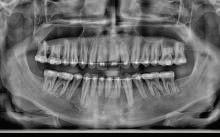

Dental Tribune Bulgarian Edition / октомври 2022 г.16 клиничен случай с алайнери Г орният латерален ре зец е вторият найчесто вродено липсващ зъб.1,2 Поради разполо жението му във видимата зона на усмивката лечение то на подобни случаи нала га мултидисциплинарен под ход, целящ отличен функцио нален и естетичен резултат. Налице са няколко лечебни мо далности, свързани с различ но разпределение на място то: първият вариант е орто донтско отваряне на място и възстановяване на липсва щия зъб с конструкция, под държана от съседните зъби3 или от имплант4, докато при втория подход разстоянията се затварят и премоларът заема мястото на канина.5 Изборът на лечебен подход трябва да бъде направен съв местно от зъболекар и паци ент въз основа на очакванията на последния и предвиди мостта на лечението. Множе ство фактори влияят върху това решение, като напри мер типа малоклузия, размера, формата и цвета на кучеш ките зъби6, оклузалните вза имоотношения (овърджет и овърбайт), лицевия профил, дължината на зъбната дъга и несъответствията в разме ра на зъбите.7 В настоящата публикация се разглежда случаят на жена в зряла възраст с вродена лип са на горен ляв латерален резец. Бяха приложени про зрачни алайнери за отваряне на място за единичен им плант и бяха постигна ти функционална оклузия и отлична естетика. ПРЕДСТАВЯНЕ НА СЛУЧАЯ Диагноза Пациентката бе на 32 годи ни, когато лечението започна, и първоначалното ѝ състоя ние бе следното (фиг. 1–3): липсващ горен ляв латерален резец; клас II, подклас I малоклузия; отклонение на горната сре динна линия вляво; Доклад на клиничен случай ЛЕЧЕНИЕ С АЛАЙНЕРИ НА ПАЦИЕНТ С АГЕНЕЗИЯ НА ЛАТЕРАЛЕН РЕЗЕЦ Д-р Iro Eleftheriadi и д-р Christodoulos Laspos, Гърция и Кипър Фиг. 1a–h Предоперативни лицеви и интраорални снимки. Фиг. 2a–e Дигитални модели преди началото на лечението. Фиг. 3 Панорамна снимка преди лечението. Фиг. 1a Фиг. 1d Фиг. 1f Фиг. 2a Фиг. 2d Фиг. 2b Фиг. 2e Фиг. 3 Фиг. 2c Фиг. 1b Фиг. 1e Фиг. 1g Фиг. 1h Фиг. 1c

Dental Tribune Bulgarian Edition / октомври 2022 г. 17клиничен случай с алайнери леко струпване в долната че люст; несъответствие по Болтън (мандибуларен излишък от 3.06 мм във фронталната зона и общо 1.47 мм); издължено лице с лицева аси метрия; конвексен профил с ретруди рана долна челюст и проми нентен нос. На мястото на зъб #46 бе на лице имплант, а зъби #16 и 26 са ендодонтски лекувани. Тези зъби бяха асимптоматич ни, затова бе взето решение да се прави релечение само при нужда. Мъдреците липсваха. Анализът на телерентгеногра фията (фиг. 4) показа ретрог натна мандибула (SNB: 74.2°) и нормална инклинация на резците както в

Цели на лечението и лечебен план Целите на лечението бяха следните: нивелиране и подреждане на зъбите и в двете зъбни дъги; отваряне на пространство за липсващия латерален резец; коригиране на отношенията при канините и моларите до клас I; и корекция на отклонението на срединната линия. Лечебният план включваше: корекция на отношенията при кучешките зъби и мола рите до клас I с дистализира не на максилата; отваряне на пространство в областта на #22 за поставя не на единичен имплант; корекция на срединната ли ния; и създаване на място за раз ширяване на зъб #12 и апрок симална редукция в долната челюст с цел подобряване на несъответствието по Болтън и осигуряване на подобра оклузия. Изпълнение на лечебния план Този случай бе изпълнен със системата за алайнери Invisalign (Align Technology). Одобреният първоначален лечебен план предвиждаше 49 алайне ра с дистализиране на задни те горни зъби до клас I (прибли зително с около 3.5 мм; фиг. 5). За бъдещия имплант в областта на липсващия латерал бе планирано пространство от 6.5 мм, докато във фронталния сегмент на долната челюст бе предвидена апроксимална редук ция. В дясната страна бутон за ластици клас II бе поставен на зъб #47 вместо на зъб #46, за да не се увреди короната на импланта. Понеже пациентката жи вееше в чужбина,

следните казуси: недобра оклу зия в дисталните зони по вре ме на дистализирането на гор ната челюст и накланяне на зъб #21 (фиг. 7). Последното се дължи на липсата на компози тен атачмънт на този зъб, каквото не бе зададено в пър Фиг. 4 Телерентгенография и цефалометричен анализ преди началото на лечението. Фиг. 5a–e Одобреният първоначален лечебен план. Фиг. 6a–h Снимки по време на лечението, показващи нуждата от внасяне на някои корекции. Фиг. 4 Фиг. 5a Фиг. 5d Фиг. 6a Фиг. 6d Фиг. 6f Фиг. 6b Фиг. 6e Фиг. 6g Фиг. 6h Фиг. 6c Фиг. 5e Фиг. 5b Фиг. 5c

Dental Tribune Bulgarian Edition / октомври 2022 г.18 воначалния план. Тези пробле ми бяха адресирани чрез допъл нителна поръчка на алайнери с торк контрол и зададено екст рудиране на задните зъби с цел установяване на добри оклузал ни контакти в дисталните об ласти, като бяха предвидени и оптимизирани атачмънти с контрол над корените за корекция на ангулацията на макси ларните резци (фиг. 8). Резултати от лечението Панорамната рентгено графия след ортодонтското лечение показа благоприятна паралелна позиция на съседни те зъби, подходяща за поставя не на имплант в областта на #22, както и конвергенция на ко рените на зъби #44 и 45 (фиг. 9), но преценихме, че няма да от деляме допълнително лечебно време за коригирането ѝ поради факта, че пациентката бе мно го доволна от постигнатия до момента резултат. След при ключване на лечението бяха постигнати отлични взаимо отношения клас I при мола рите и канините, а срединни

съвпадаха. Върху им

(LFH: 56.5 mm) и размерите на меките тъка ни останаха непроменени. На клонът на горните резци бе за пазен (Ui–FH: 115.8°), а долните резци бяха леко наклонени ве стибуларно (Li–APog: 30°; фиг. 16). ДИСКУСИЯ Липсата на зародиш на по стоянен горен латерален резец е налице при 3.5–6.5% от евро пеидната раса, като при жени е по-честа, отколкото при мъ жете в съотношение 3:2.8–10 Възможни са няколко лечебни подхода, включително замя ната му с преоформен канин, отваряне на място чрез орто донтско лечение и протетич но възстановяване, както и ав тотрансплантация. Устано вено е, че изборът за затваря не на място или за отваряне то му все още подлежи на дис кусия сред ортодонти и проте зисти.11,12 Според литературните дан ни затварянето на простран ството и замяната на липсва щия латерал с канин се предпо чита в случаи на едностранна липса на зародиш, балансиран профил, кучешки зъби и премола ри със сходна форма и цвят, дву челюстна протрузия или клас II малоклузия.13–15 Отваряне на пространство по-често се изби ра при клас I, наличие на диасте ми и треми в горната зъбна дъга или голяма разлика в размерите на канини и премолари.16 Скорошно проучване е уста новило, че изборът на лечение при конгенитално липсващ ла терал е пряко свързан със след ните фактори17: възрастта на пациента при започване на лечението; индивидуалните особености при всеки конкретен случай; и сътрудничеството между специалистите в лекуващия екип. Макар да има проучвания, фа воритизиращи леченията със затваряне на място11,18, всеки случай трябва да бъде оценяван индивидуално. В презентирания в тази статия случай бе взето решение за отваряне на мяс то и протетично възстановя ване, понеже целта бе да се по стигнат клас I отношения при канините и моларите, както и по-широка усмивка. За да се из бегнат компромиси, след лече нието бе постигнат клас I при моларите и кучешките зъби, несъответствието по Болтън бе подобрено и срединната ли ния бе коригирана. Други изслед вания демонстрират отлични естетични и функционални ре зултати при лечение с отваря не на място и протетична ре хабилитация.19 И двете лечеб ни модалности са подходящи за третиране на вродена лип са на зародиш на латерал и да ват сходни функционални и па родонтални резултати20, като при едно проучване

ти и клас II ластици е устано вено, че осигурява достатъч на дистализация без промяна на лицевата височина.23 Както се видя от цефалометричния анализ, точно това бе постиг нато и в представения случай като се има предвид, че лице вата височина остана същата като първоначалната. Предвид леката тенденция към дистал Фиг. 8a–e Поръчаните допълнителни алайнери. Фиг. 9 Панорамна рентгенография след края на лечението. Фиг. 10a–c Странични (а и с) и фронтална интраорални снимки след края на ортодонтското лечение и поставянето на импланта (b). Зъб #12 все още не беше протезиран. Фиг. 11а и b Оклузални снимки след ортодонтското лечение. Фиг. 7a Фиг. 8a Фиг. 7d Фиг. 8d Фиг. 9 Фиг. 10a Фиг. 10b Фиг. 10c Фиг. 11bФиг. 11a Фиг. 7b Фиг. 8b Фиг. 7e Фиг. 8e Фиг. 7c Фиг. 8c Фиг. 7a–e Интраоралната ситуация по време на лечението. клиничен случай с алайнери

Dental Tribune Bulgarian Edition / октомври 2022 г. 19 на отворена захапка е устано вено, че финалното адаптиране и подобряване на оклузалните контакти се установяват след повече от три месеца след лече нието.24 Следователно подобря ване на ситуацията и плътни оклузални контакти се очак ват след края на лечението. Що се отнася до избора за замест ване на липсващия латерален резец с единичен имплант и протезирането му, установе но е, че това е най-често при лаганата лечебна алтернати ва.25 Съседните зъби остават интактни и следователно най голямото предимство на този подход е съхраняването на здра ви зъбни структури. Изборът ни на лечебен план бе базиран на детайлна мул тидисциплинарна диагноза и планиране, а те категорично са ключови за постигане на оп тимални индивидуални резул тати при пациенти

но

между членовете на екипа и пациента. ЗАКЛЮЧЕНИЕ Случаите на липсващи лате рални резци трябва да бъдат третирани от перспектива та на интердисциплинарна ди агностика и лечение. Употреба та на софтуера ClinCheck има доказани предимства за плани ране, комуникация между кли ницистите и пациента и фи нализиране на лечебния план, като се адресират всички же лания и притеснения на паци ента. Настоящият доклад на клиничен случай доказва, че с помощта на съвременните ме тоди един успешен екип от спе циалисти (ортодонт, консерва тивен зъболекар и хирург) може да се стреми към отлични ре зултати и да постига есте тични и функционални усмив ки без компромиси. Ред. бел.: Статията Treatment of a patient with a congenitally missing lateral incisor using aligners: A case report е пуб ликувана за първи път в сп. aligners–international magazine of aligner orthodontics, бр. 1, издание 1/2022. Библиографията е налична при издателя. За авторите: Д-р Iro Eleftheriadi завършва дентална медицина в Атинския университет, а магистратурата си по медицинска статистика – през 2014 г. в Публичния университет в Атина, Гърция. Специализира ортодонтия и завършва през 2017 г. в Университета в Тел Авив, Израел. Предстои ѝ да защити докторан тура във Факултета по дентална медицина към Университета в Атина, Гърция. Д-р Christodoulos Laspos завършва дентална медицина през 1995 г. в Атинския университет, Гърция, а магистратурата си завършва през 1999 г. във Фа култета по дентална медицина към Университета в Тенеси, Мемфис, САЩ. Печели стипендия и специализира лечение на пациенти с лицево-челюстни малформации в Университета в Тексас, Далас, САЩ, и е сертифициран специалист от Европейския борд на ортодонтите. Той е докторант в Универ ситета в Берн, Швейцария. От 2000 г. д-р Laspos практикува в частната си ортодонтска практика в Лимасол, Кипър. Той е основател и директор на MEDICLEFT, Кипърски център за цепки и лицево-челюстни аномалии, както и директор на фондацията Synergy, която осигурява следдипломно обучение на лекари по дентална медицина. Научен съ трудник е във Факултета по дентална медицина към Европейския университет в Кипър. Д-р Laspos изнася лекции по цял свят по теми като лицево-челюстни мал формации, ортогнатна хирургия, мултидисциплинарен подход и нови технологии в ортодонтията. Той е активен член на Европейското общество на Енгел и прези дент на Европейското ортодонтско общество. Фиг. 12а–c Финални странични (а и c) и фронтална интраорални снимки (b). Фиг. 13а и b Финални оклузални снимки. Фиг. 14 Финална снимка на усмивката отблизо. Фиг. 15 Финална екстраорална снимка на усмивката. Фиг. 16 Финална телерентгенография и цефалометричен анализ. Фиг. 12a Фиг. 13a Фиг. 14 Фиг. 15 Фиг. 16 Фиг. 13b Фиг. 12b Фиг. 12c клиничен случай с алайнери